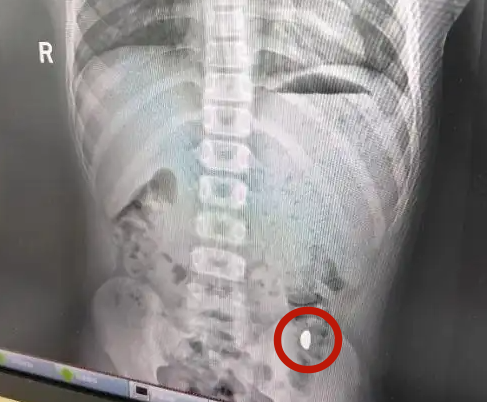

▲男童吞下10g金豆。(圖/翻攝自微博)

醫師指出,患童5天前誤吞約10克黃金,期間解2次大便未發現,目前無腹痛、嘔吐等症狀,診斷結果顯示胃內有異物。所幸去看完醫生後,當天就將該顆金豆排出來了。